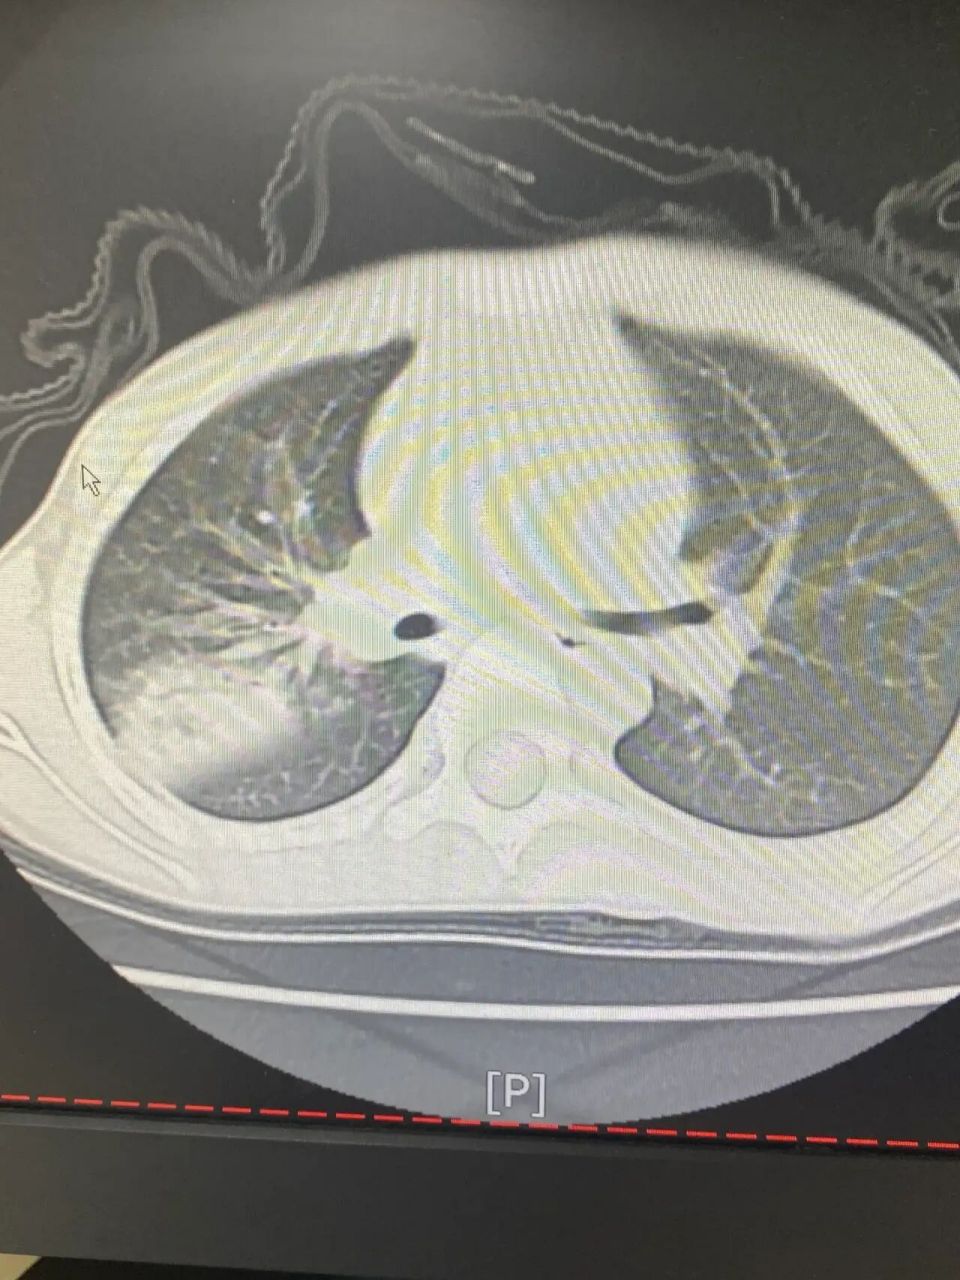

儿科最近收治,高热五天伴咳嗽,肺ct如下,支原体阳性,考虑重症肺炎(右

图片尺寸3072x4096

儿童重症肺炎,支原体肺炎严重并发症之肺水肿(ct表现)

收治11岁女童难治性支原体肺炎,重症肺炎住院治疗10天后转归复查

图片尺寸1080x1920

转到儿童医院的6岁儿童病例,重症肺炎,严重支原体感染引发的肺部炎症

图片尺寸1080x1438

5岁女童,高热数日,重症肺炎(肺实变,肺不张)支气管镜适应症

儿童重症肺炎的治疗前后对比.6岁重症肺炎,输液治疗十四天后对 - 抖音